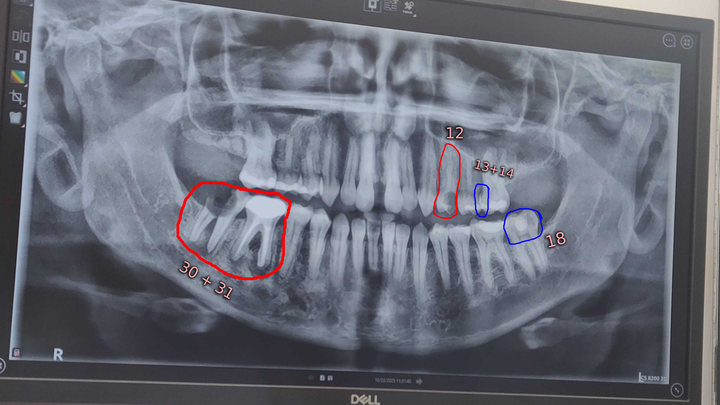

Two weeks ago, part of my back molar broke off. you can see it in the x-ray; the one that's just the roots pretty much. I had a dental appointment this past week where we discovered several pressing issues and decided different treatment options with the original cost for everything being only around $17,200USD.

However, the day after my exam, the majority of one of my front tooth (12) that I had plans to save, broke off.

In my photos, I have included the original bill for each part of the treatment plan. I'm unsure how they'll want to handle the newly ruptured tooth, but they had already suggested extraction before it was ruptured like this. It is likely that it will need to be removed and have a bone graft as well. My changes to the bill total are my own math, based on their prices included for extraction, bone graft, and implants, for the newly ruptured tooth.

Each part of this process will be expensive as you can see. But, each part can be done in different times. At the moment, getting the implants is not a primary concern. They are something I would genuinely like to do, but I want to focus on the core health issues. Which is the removal and bone graft of the teeth circled in red and the fixing of the teeth circled in blue.